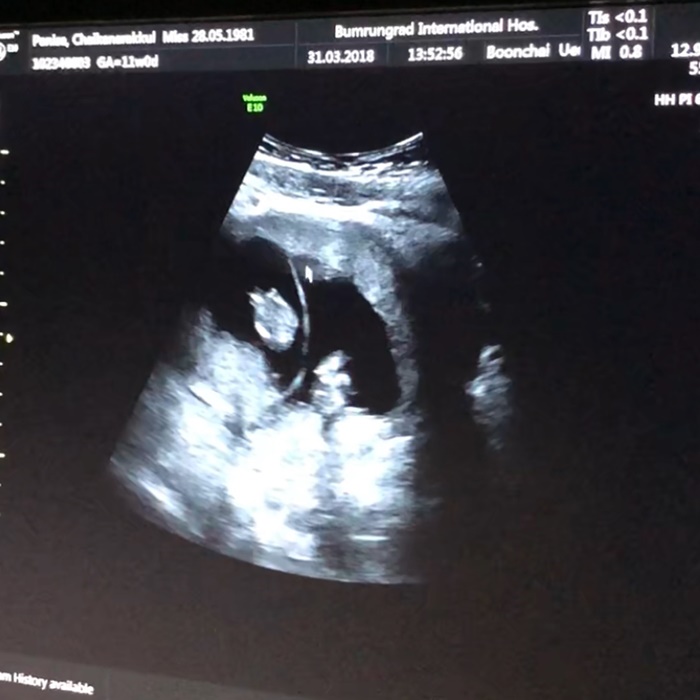

บรรยากาศที่คุ้นเคยเมื่อสามปีก่อนกลับมาอีกครั้ง...รีบขนข้าวขนของเด็กอ่อนออกมาปัดฝุ่น...คิดไปต่าง ๆ นานาว่าลูกของเราจะเป็นหญิงหรือชาย...และรอคอยวันที่จะไปอัลตราซาวด์เพื่อดูว่าลูกในท้องเป็นปกติดีหรือไม่..?? เราฝากท้องกับคุณลุงหมอบุญชัยของพี่ภัทรเหมือนเดิมครับ... แล้ววันที่คุณหมอนัดก็มาถึง...

บรรยากาศการอัลตราซาวด์ก็ดูคุ้นเคย..เหมือนย้อนเวลากลับไปอีกครั้งที่เพิ่มเติมมาคือ มีตัวน้อย ๆ อีกหนึ่งคนมาช่วยดูจอกับเราด้วย...ทุกอย่างก็ดูปกติธรรมดา...แต่มีบางอย่างที่ไม่ธรรมดาครับ..เมื่อคุณหมออมยิ้มพร้อมกับชูสองนิ้วให้กับเรา...แล้วบอกด้วยเสียงเบา ๆ ว่า "Twins" และนั่นก็คือปาฏิหารย์ในชีวิตครั้งที่ 2 ของคงกระพัน... ป.ล. จากการสืบถามญาติพี่น้องของทั้งครอบครัวผมและภรรยาไม่เคยมีประวัติการมีแฝดมาก่อน... ผมกำลังถูกลอตเตอรี่รางวัลที่ 1 โชคสองชั้น..ใช่ไหมครับ..???"